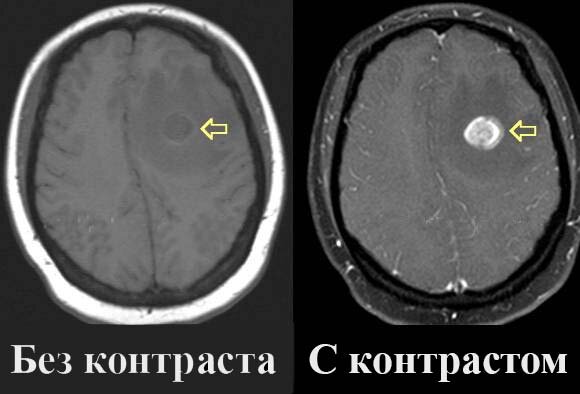

Так примерно всё выглядело, но не на мозге, а на всём теле

Я увидел эго, или как это назвать, какую-то дьявольскую вставку в себе самом. Очень быстро промелькнувший образ, но я успел его запечатлеть. Это выглядело как кусок чего-то в моём кровотоке. Вот как когда вводят контраст и видно по каким сосудам он идёт, так и я увидел эту штуку в своём теле. И это была не просто жидкость, которую можно вывести из тела, это была какая-то структура. Но я прошу, не думайте что это было что-то вроде сложного видения и я в это время лежал в эпилептическом припадке, а потом начал строить вокруг этого тысячи предположений и трактовок, нет. Мне просто на мгновение показалось что есть что-то во мне, что заставляет меня очень часто думать об этом "себе", волноваться, переживать, защищать этого "себя", везде искать угрозу этому "себе". Что-то, из-за чего я всё воспринимаю в основном на "свой" счёт, из-за чего желаю чтобы все медали дарили мне и чтобы меня ни за что не считали обычным.